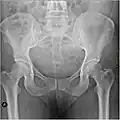

Рентгеновский снимок женского таза в прямой проекции, может использоваться для уточнения размеров таза